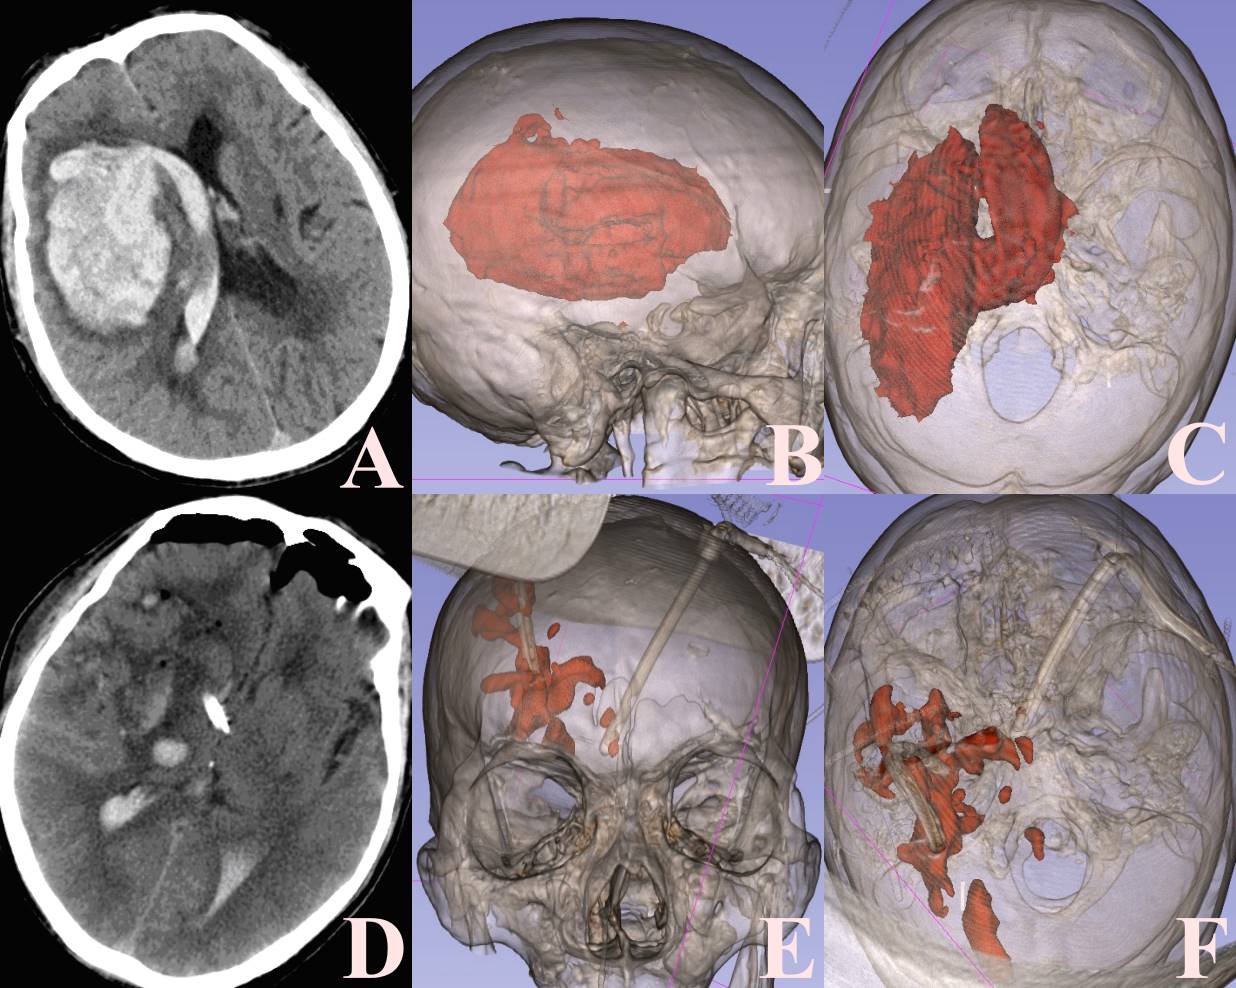

患者62岁男性,突发意识不清4小时急诊入我院。患者既往有高血压病史,当时意识呈中度昏迷,GCS评分2 + 1 + 4,双侧瞳孔2 mm固定,双侧巴氏征阳性。急查颅脑CT检查提示右侧基底节区脑出血并破入脑室,脑室铸型(图1)。评估患者病情及影像学检查结果,有急诊手术指征,经讨论我们最终制定了神经内镜联合硬通道手术方案。全麻成功后,取同侧冠状缝前纵行直形切口,逐层切开皮肤直达骨膜,铣刀游离骨瓣大小约2 × 2 cm,“十”字或弧形剪开硬脑膜,以冠状缝前2 cm及中线旁开2~3 cm作为穿刺点,根据3D Slicer软件设计的穿刺方向,尽量避开脑沟及皮层血管,将一次性透明扩张器准确穿刺入血肿内,即建立硬通道,使用高清硬质神经内镜观察镜,吸除血肿,确切止血(图2);随即调整硬通道方向,通过破孔进入脑室内进行血肿清除,在神经内镜直视下留置引流管,反复温盐水(33℃~36℃)冲洗术区,未见活动性出血,回纳骨瓣,并逐层缝合手术切口,安全起见对侧亦留置脑室外引流管。

注:(A) 术前颅脑CT检查提示右侧基底节区脑出血并破入脑室,脑室铸型;((B) (C)) 术前3D Slicer软件重建的图,精确计算脑出血量,并制定安全的手术通道;(D) 术后第1日复查的颅脑CT检查,血肿已基本清除,达到减压效果;((E) (F) 术后3D Slicer软件重建的图,观察血肿清除效果,并计算残余血量。

Figure 1. Case report

1. 病例汇报

患者术后第1日内均进行颅脑CT检查,通过3D Slicer软件精确计算残留血肿(图1),分别得出两种术式的血肿清除率。结果显示,神经内镜联合硬通道技术在血肿清除率方面优于传统开颅显微镜手术[(94.7 ± 4.8)% vs. (87.8 ± 11.4)%, P = 0.012]。尤其适用于颅内深部血肿,即基底节区脑出血,伴或不伴有脑室内血肿[(94.8 ± 4.6)% vs. (86.8 ± 13.0)%, P = 0.026]。神经内镜手术时间明显短于传统开颅手术时间[(2.2 ± 0.5)% vs. (4.4 ± 1.1)%, P < 0.05]。通过定期随访患者,我们得出格拉斯哥预后评分(GOS评分),神经内镜组患者的远期预后往往好于传统开颅显微镜手术组[(4.05 ± 0.65)% vs. (3.41 ± 1.27)%, P = 0.041]。